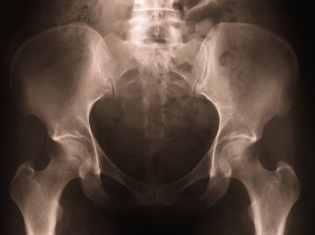

Researchers measured different bone characteristics, including bone mineral density, cortical thickness and thickness of the femoral neck.

Bone mineral density is the amount of mineral matter in the bones. Lower bone mineral density - like that which occurs in osteoporosis - is often a sign of weak bones. Cortical thickness is the thickness of the tissue that forms that outer shell of most bones. The femoral neck is the part of bone just below the hip joint.

Compared to participants with adequately controlled blood sugar and those without diabetes, diabetes patients with poorly controlled blood sugar had:

- 1.1 to 5.6 percent higher bone mineral density

- 4.6 to 5.6 percent thicker cortices

- 1.2 to 1.8 percent narrower femoral necks

"Poor [blood sugar] control in type 2 diabetes is associated with fracture risk, high bone mineral density, and thicker femoral cortices in narrower bones," the authors conclude.

The authors suggested that apparently "strong" bones of diabetes patients may in fact be fragile because the bones do not repair well. This fragility may be caused by the buildup of microcracks (small cracks) or cortical porosity (the amount of pores, or how much of the bone is actually empty space, in the cortical bone). However, the study's results did not explain the exact cause of increased fracture risk among patients with poorly controlled type 2 diabetes.